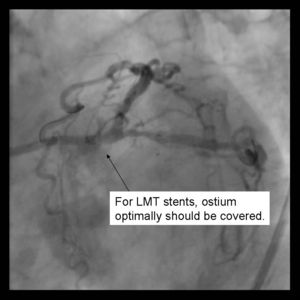

Benefits:

Ensures complete coverage of the side branch ostium Immediate patency of parent and side branch Access to both branches maintained through procedure No need for final kissing balloon